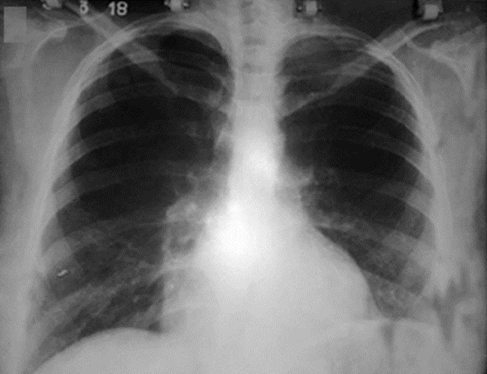

El día 30 de diciembre de 2017 al observar en el estudio radiológico evolutivo mejoría evidente, se aplica una segunda dosis igual a la anterior. En esta ocasión el líquido que se obtuvo del lavado y la aspiración fue claro.

La evolución clínica y radiológica fue satisfactoria. La sonda de pleurotomía fue retirada el día 31 de diciembre de 2017 y la enferma es trasladada al hospital materno provincial el día 2 de enero de 2018 para continuidad y seguimiento del embarazo, el cual culmina sin complicaciones por parto eutócico. Se realiza control radiológico a los 30 días del puerperio, el cual es normal (Fig. 2).